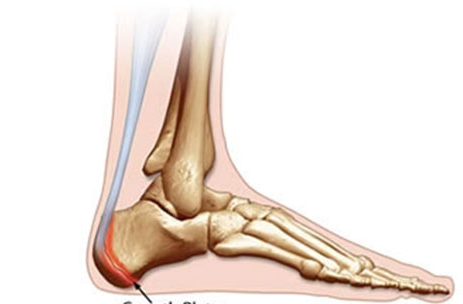

Sever's Disease is used to describe pain in the back of the heel that comes from an inflamed growth plate in your child's heel. Sever's Disease commonly occurs in children from the ages 8-15. The muscles and tendons become tight as the bones shift and grow. This causes pain when walking or participating in athletic events that require running and jumping. WHAT CAUSES SEVER'S DISEASE? Sever's Disease is thought to be caused by several reasons: Growth spurts. The muscles and tendons become tight due to rapid bone growth. Overuse. Sever's Disease can also occur in children who are athletically active and overwork his or...